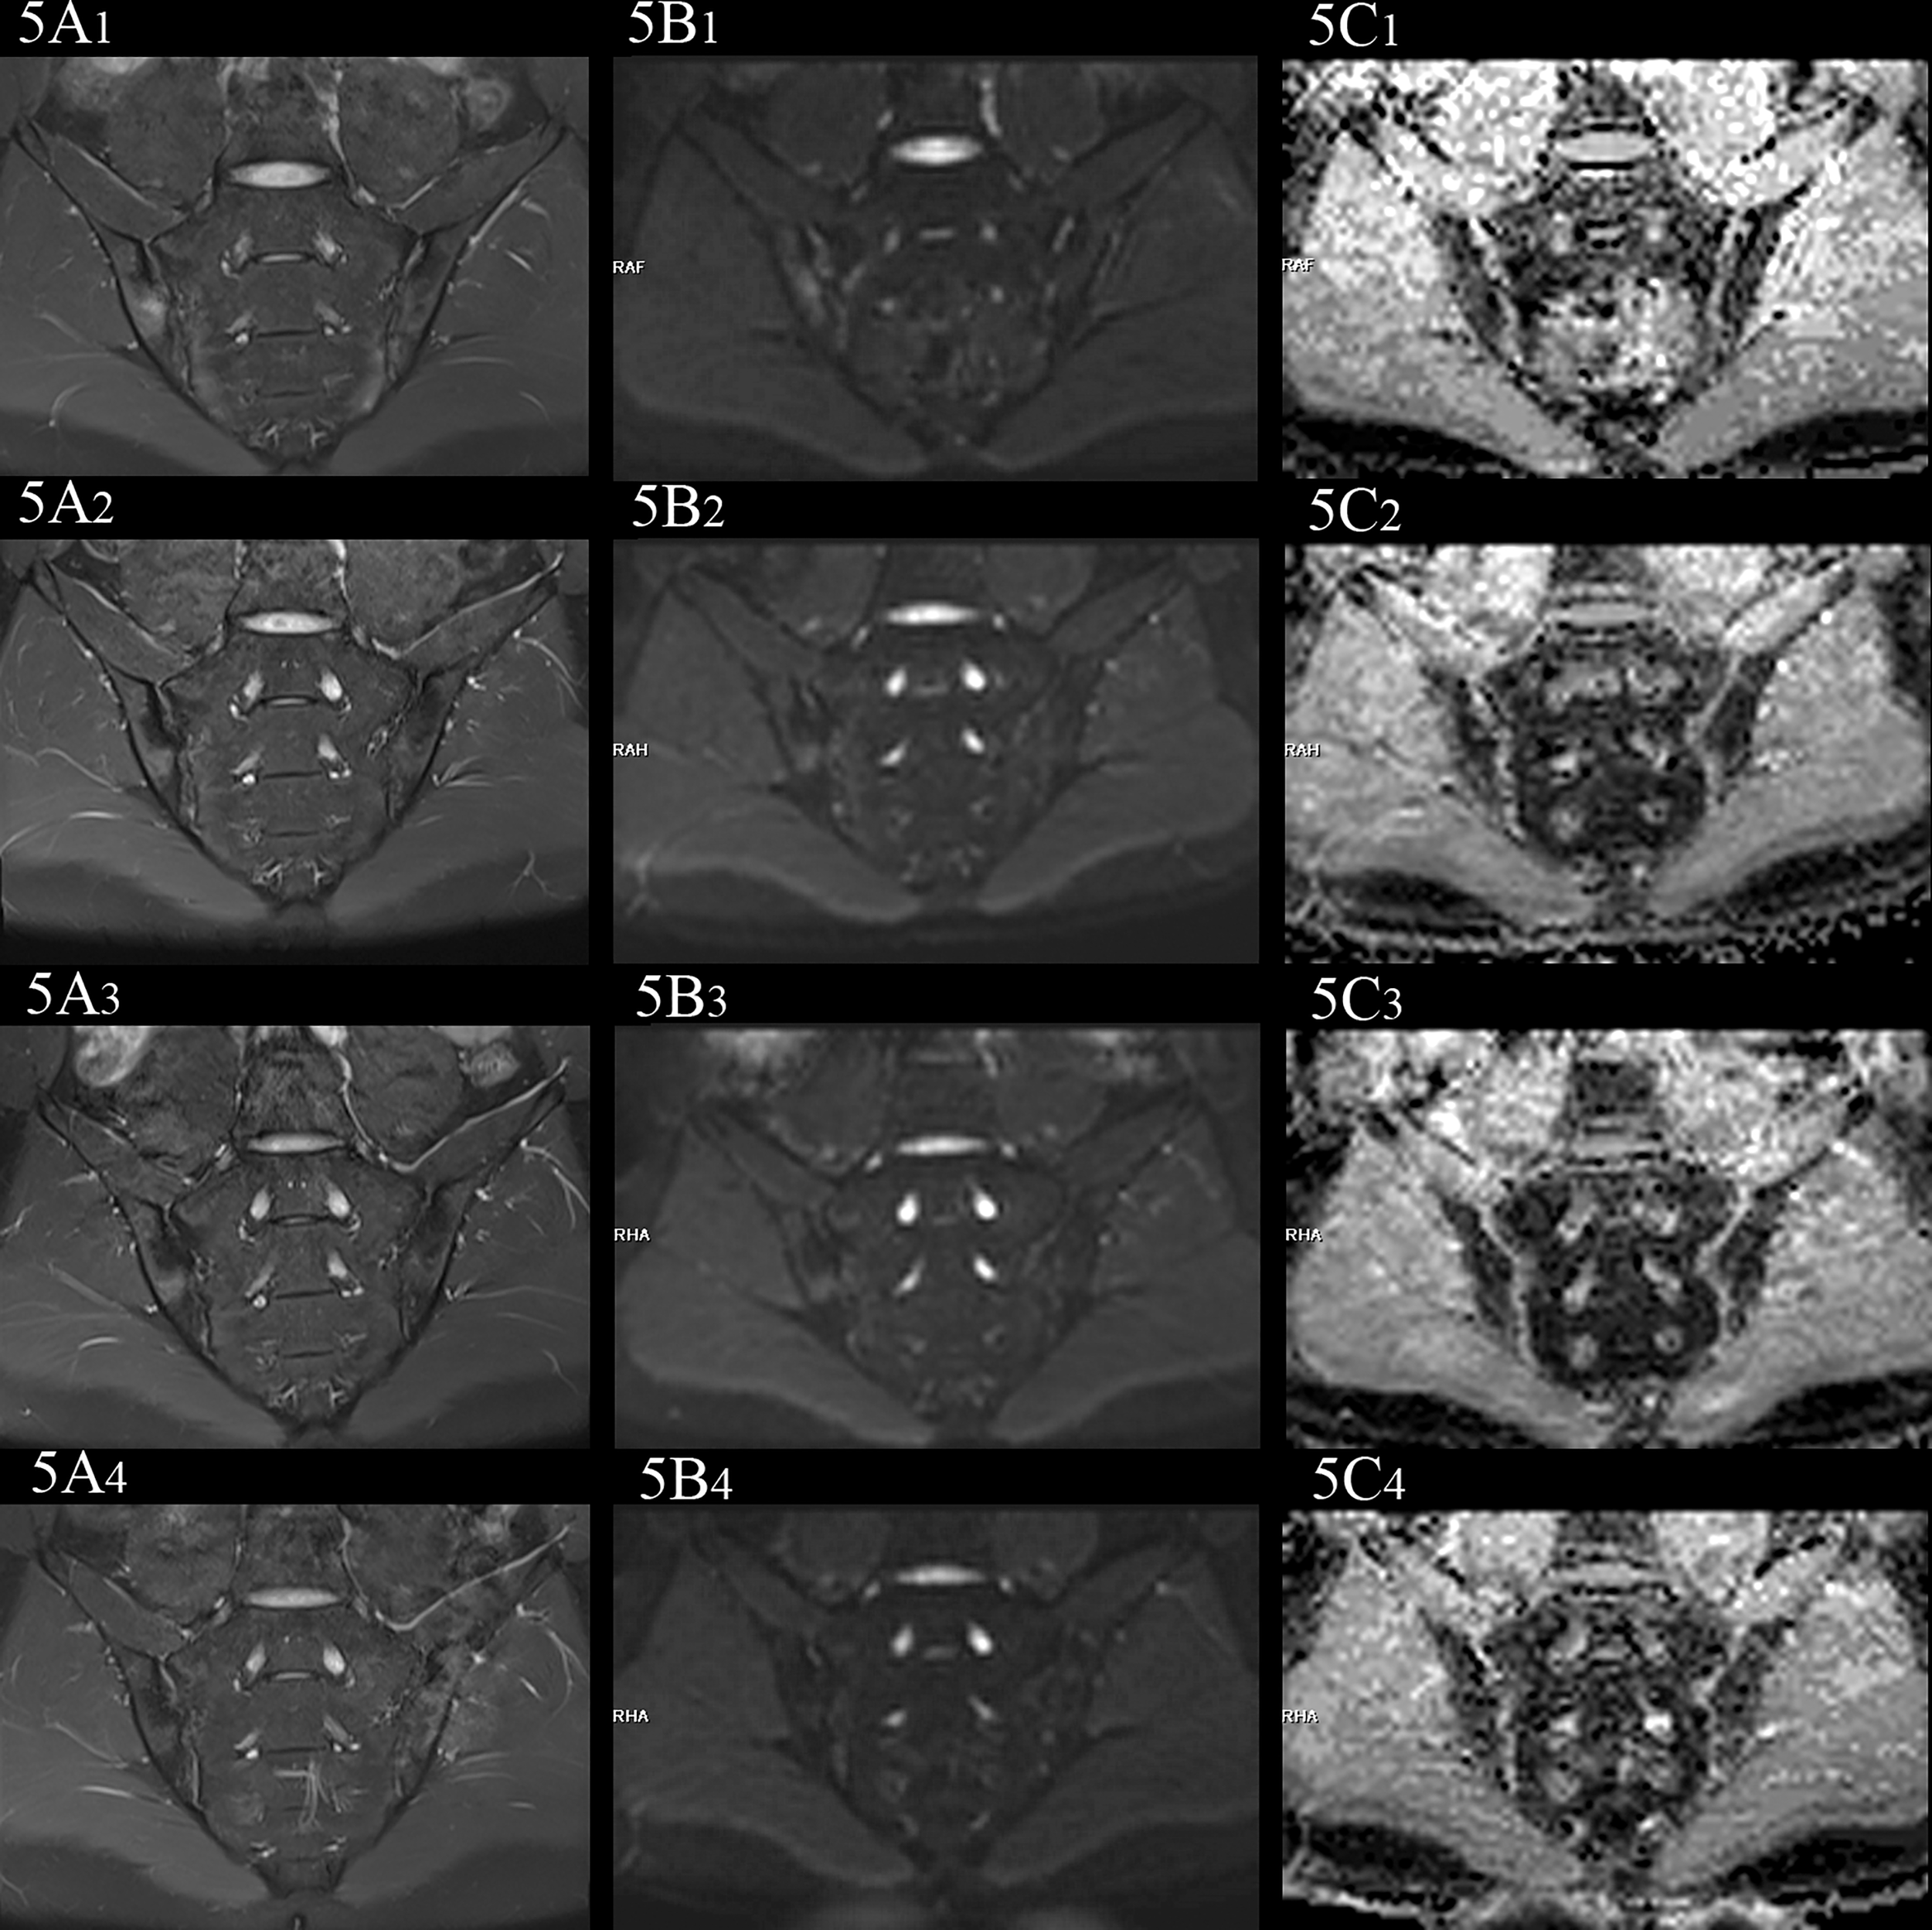

Figure 5

female, 27 years old, HLA-B27: +, CRP:31.5mg/L, ASDAS-CRP:4.6, belonged to active group and the treatment group; (A(1-4)-C(1-4)) showed the same patient before treatment and 3 weeks, 6 weeks and 12 weeks after treatment, respectively. (A(1-4)) showed the coronal plane of PDWI-fs; (B(1-4)) showed the coronal plane of RESOLVE DWI (b=50,500,700s/mm2); (C(1-4)) showed the ADC maps (b=50,500,700s/mm2). In patients with effective treatment, the ASDAS-CRP score decreases with the increase of the treatment cycle (4.6, 3.5, 2.2, 1.5). (A(1-4), B(1-4)) PDWI-fs and RESLOVE DWI showed the gradual decrease of the signal in the subchondral bone of bilateral sacroiliac joints; (C(1-4)) showed the ADC values in the bone marrow area of the lesion decreased gradually (1.047, 0.710, 0.666, 0.648×10-3 mm2/s).

In the treatment group, the signal intensity of subchondral bone marrow decreased in different degrees in 3 weeks, 6 weeks and 12 weeks after treatment. PDWI-fs sequence showed that the signal intensity of subchondral bone marrow in sacroiliac joints decreased in varying degrees (Figure 4A(1-4), 5A(1-4)); DWI signal decreased in varying degrees (Figure 4B(1-4), 5B(1-4)); ADC value showed a downward trend (Figure 4C(1-4), 5C(1-4)); ADC values decreased with ASDAS-CRP values, synchronously (Figure 9). The median ADC values of the treatment group before treatment, 3 weeks, 6 weeks and 12 weeks after treatment were 1.177×10-3 mm2/s, 0.886×10-3 mm2/s, 0.668 ×10-3 mm2/s and 0.519 ×10-3 mm2/s, respectively.